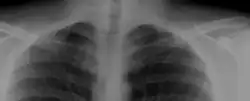

Most cases of cervical ribs are not clinically relevant and do not have symptoms;[11][12] cervical ribs are generally discovered incidentally, most often during x-rays and CT scans.[7][8][10] However, they vary widely in size and shape,[7] and in rare cases, they may cause problems such as contributing to thoracic outlet syndrome,[11] because they press on the nerves.[11][13]

On imaging, cervical ribs can be distinguished because their transverse processes are directed inferolaterally, whereas those of the adjacent thoracic spine are directed anterolaterally.[15]